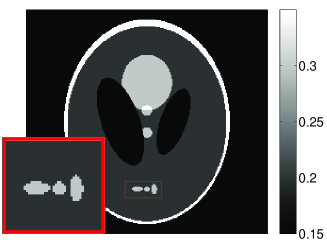

• [63] C. W. Dodge, A rapid method for the simulation of filtered X-ray spectra in diagnostic imaging systems (ProQuest, 2008).